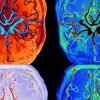

Uyku sırasında beynin nasıl bir "filtre" gibi çalıştığı ilk kez bu kadar net görüntülendi. Geliştirilen yeni MR tekniğiyle, zihnimizin gece boyu atıklardan arınmak için kullandığı muazzam sistemi ve sıvı hareketlerini adım adım izlemek artık mümkün.

Oulu Üniversitesi araştırmacıları, beyin sıvısı içindeki su moleküllerinin hızını ve yönünü takip edebilen hassas bir manyetik rezonans görüntüleme (MRG) yöntemi geliştirdi. Yapılan testler sırasında, denekler uykuya geçtiğinde kan damarlarının genişlediği ve genel tansiyonun düştüğü gözlemlendi. Ancak asıl şaşırtıcı bulgu, damar duvarlarındaki dalgalanmalar ile nefes alışveriş ritminin yarattığı sıvı hareketliliğinin artmasıydı. Bilim insanları, bu ritmik değişimin beyin dokusundaki suyun çok daha etkili bir şekilde süzülmesine imkan tanıdığını vurguluyor.

Projenin başındaki isim Profesör Vesa Kiviniemi, bu yeni nesil görüntüleme tekniğinin yaşlılığa bağlı zihinsel sorunların takibinde önemli bir rol oynayacağını belirtiyor. Geçmişte bu tür akışları izlemek için vücuda dışarıdan manyetik maddeler enjekte edilmesi gerekirken, Kiviniemi ve ekibi "ultrahızlı MRG" sistemiyle bu zorunluluğu ortadan kaldırdı. Bu sistem sayesinde kafatası içindeki su moleküllerinin saniyeler içindeki dalgalanmaları dışarıdan bir müdahale olmaksızın izlenebiliyor.